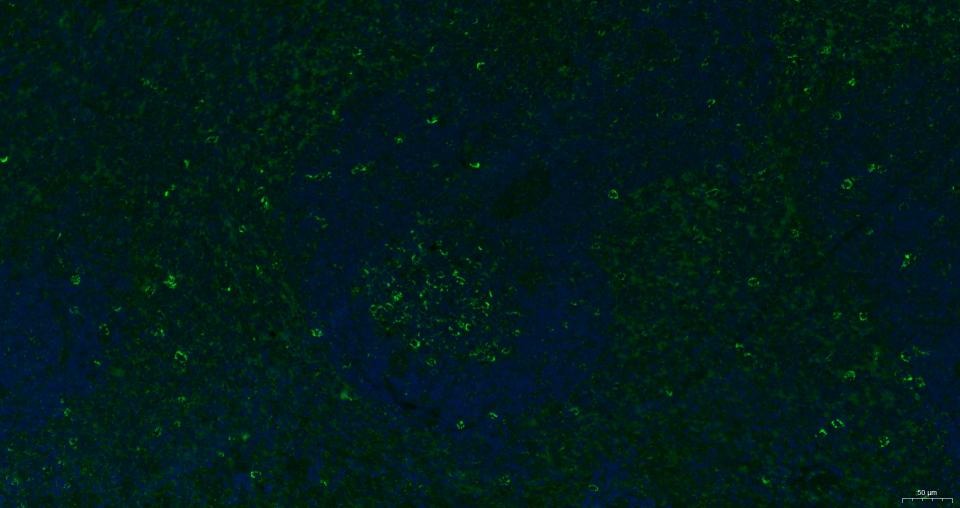

3. Paraformaldehyde-fixed, paraffin embedded Mouse spleen; Antigen retrieval by boiling in sodium citrate buffer (pH6.0) for 15 min; Antibody incubation with CXCR4 Polyclonal Antibody, Unconjugated (TMAB-00509) at 1:200 overnight at 4°C. Followed by conjugated Goat Anti-Rabbit IgG antibody (green), DAPI (blue) was used to stain the cell nucleus.